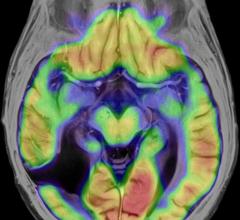

February 19, 2016 — A new way to analyze magnetic resonance images (MRI) data appears to reliably distinguish between ...

Learn more about GenIQ, a new post-processing application for assessing the vascular properties of brain, liver, prostate and breast tumors for initial as well as follow-up examinations.